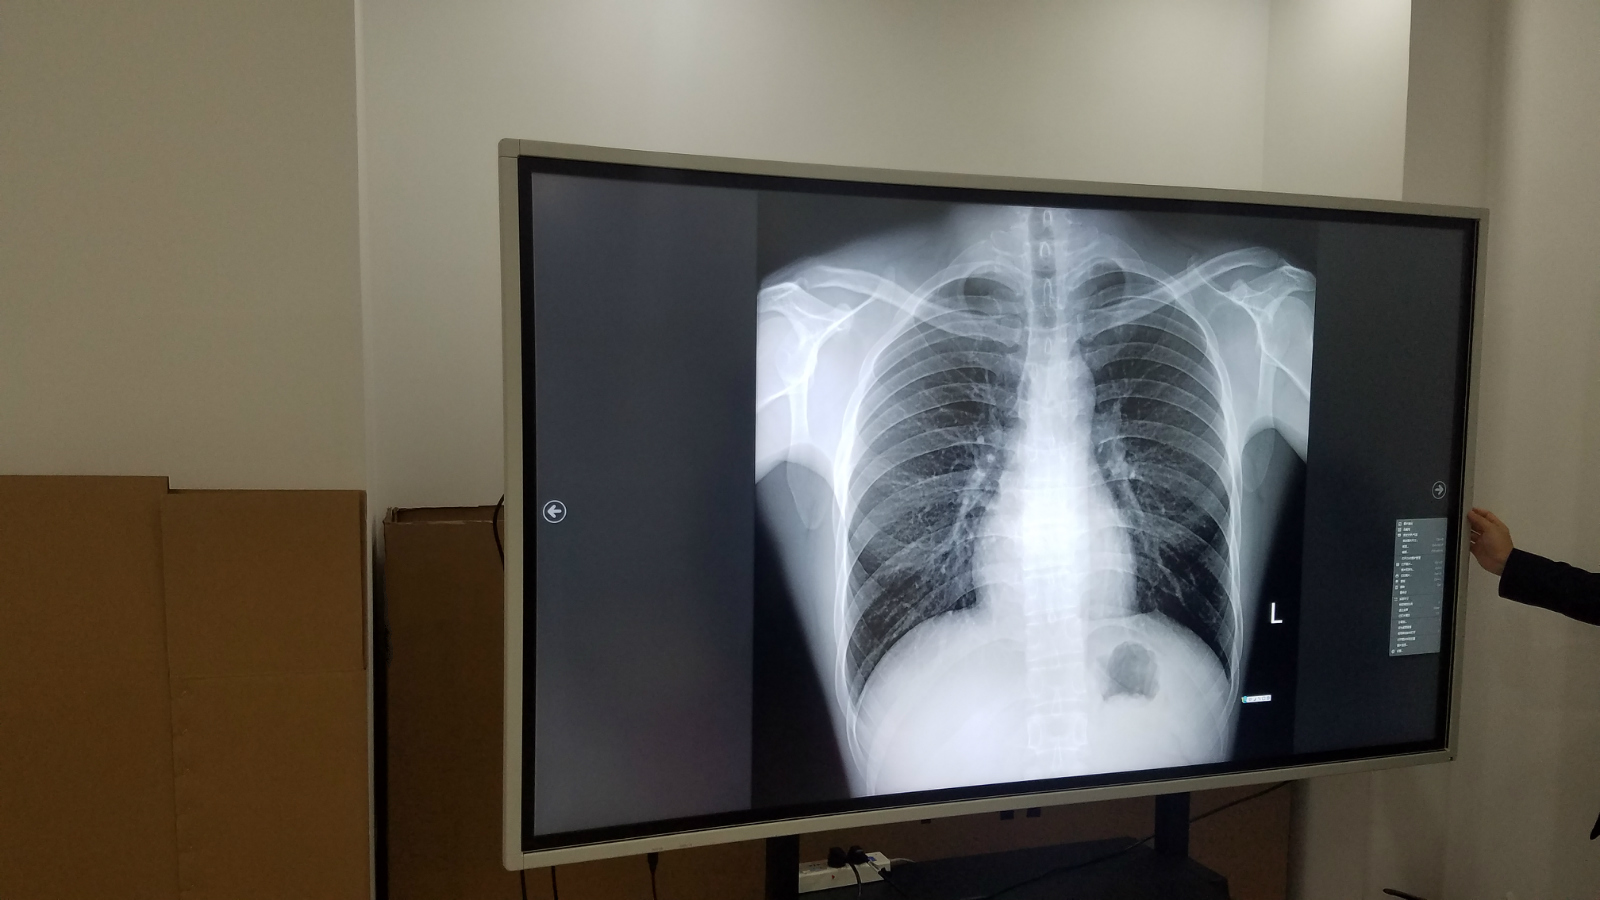

德恪商用本着“德行天下,恪尽职守,持续为客户创造最大价值”的理念,针对医院会诊,远程医疗,跨区域诊断,手术综合应用,医疗教学等应用场景而设计推出专业会诊大屏,尺寸涵盖:65寸,75寸,86寸,98寸,完全符合Dicom标准,满足医疗影像稳定一致的显示需求;具有超高分辨率、稳定亮度、忠实色彩还原、使用寿命长的优点; 支持一屏多显,可链接医院多种系统(如PACS、HIS系统),满足医院多种诊断及手术作业等需求。

小编这就带大家去看看DEKCO品牌98寸会诊大屏工艺展示实物拍摄效果:

德恪DEKCO会诊大屏无论是从功能实现上还是对灰阶显示参数指标,甚至信号接口,相较于商用显示器而已,无疑是提出了更高的要求,德恪商用由最初的“液晶显示系统解决方案提供商”的定位,现今添加了“医疗影像显示系统解决方案提供商”,给用户提供更优质,高品质的医疗会诊大屏解决方案。